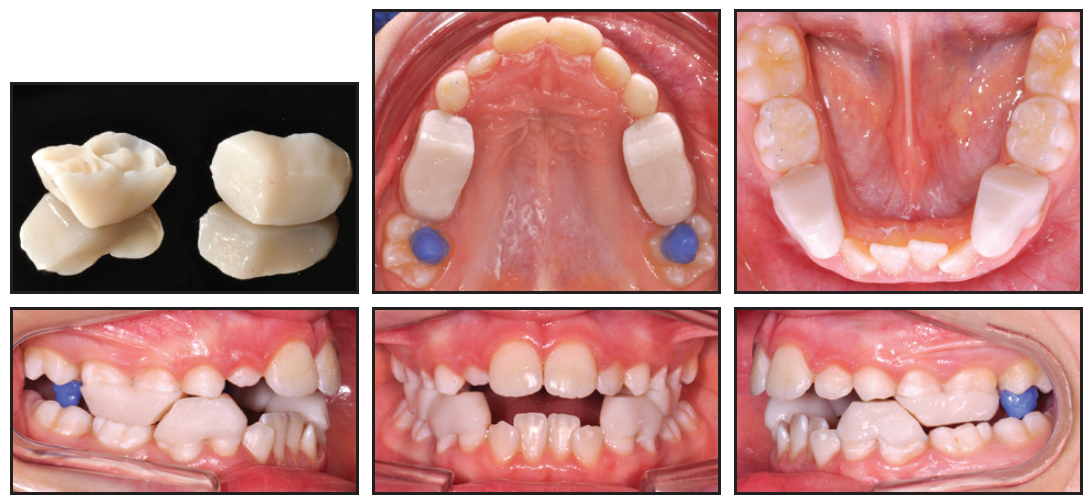

Two-phase treatment of Class II cases can be a particular challenge when it comes to practice efficiency. As observed by Dr. Héctor Luis Rodríguez in his article, “Long-Term Stability of Two-Phase Class II Treatment with the Carriere Motion Appliance,” “The optimal timing for treatment of Class II malocclusions remains controversial. Some clinicians believe strongly that it is advantageous to begin treatment in the mixed dentition before adolescence, while others are convinced that early treatment is often redundant.” Many practitioners I know have refused to perform two-phase treatment because of the overall time required. Research has shown that two-phase treatment is less efficient than single-stage comprehensive treatment, resulting in a lower profit margin per case.1,2 Still, many practitioners see a physiological advantage to two-phase treatment, especially in skeletal Class II cases. This has created a demand for a more efficient way of delivering such treatment. The Carriere Motion Appliance has become increasingly popular because it avoids the inefficiency of headgear and other Class II modalities that depend on patient compliance. There is no arguing that Dr. Rodríguez’s case shows a beautiful outcome while having been treated as efficiently as possible over two phases.